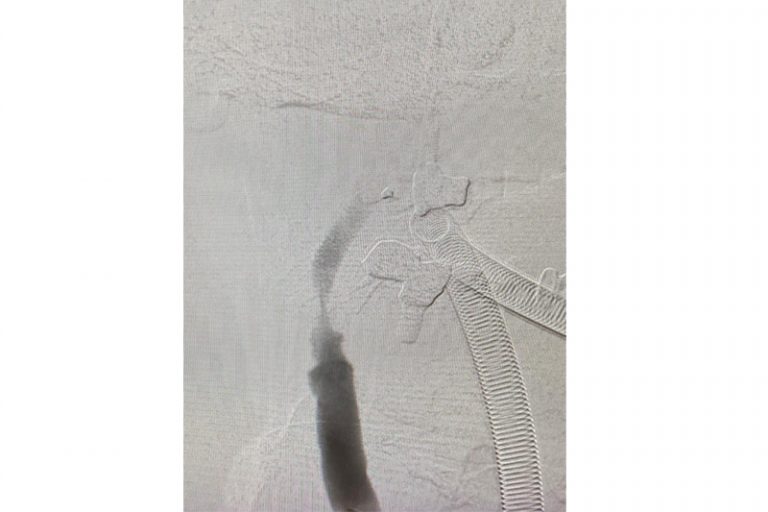

圖:導管遊走到病人右邊的頸和腦部血管大動脈,進行機械式血栓吸取

羅先生被送往私家醫院的第一步是進行緊急磁力共振造影,報告顯示羅先生右邊頸和腦部血管大動脈全部都被血栓堵塞着,右邊大腦缺血水腫,導致左邊手腳冇力和神智半昏迷。經過腦血管外科醫生的診斷和急救,在全身麻醉下,醫生使用尤如髪絲微細的導管,經過病人右邊大腿的腹股溝的大動脈而入,導管再經過腹部和胸腔的大動脈一直向上,遊走到病人右邊的頸和腦部血管大動脈,進行機械式血栓吸取內血管治療急救。